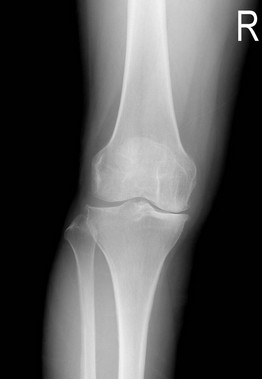

膝痛

膝痛诊断应遵循骨科疾病诊断的一般规律: 详细地询问病史,包括起病时间、诱因、外伤史、疼痛持续时间、疼痛性质、加重或缓解的因素等;细致的体格检查: 视、触、动、量及各种特殊检查;恰当的辅助检查: 如X线、CT、MRI,外周血及关节液检查等。在诊断膝痛时如能掌握年龄、外伤史、疼痛部位、典型的体征等几个要点,可提高诊断率。尤其是病史的收集非常重要,结合病人的因素一般可大概做出诊断,再借助相关辅助检查一般可确诊。有时诊断较为困难时,可能需要病理活检。